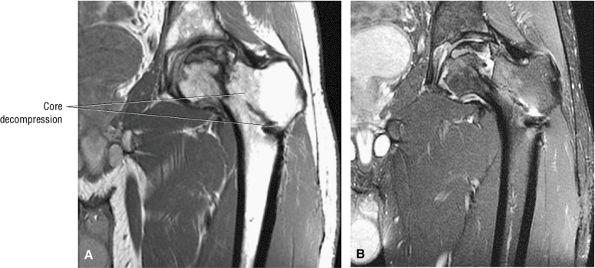

FIGURE 3.88 ● Post-core decompression for an ischemic focus with associated subchondral fracture without femoral head collapse. Arthroscopy has been performed for stage IV or post-collapse patients who are also candidates for osteotomy or vascularized graft. Delamination of articular cartilage is treated with débridement and core decompression, although improvement may be limited. (A) Coronal T1-weighted image. (B) Sagittal FS PD FSE image.

FIGURE 3.89 ● Post-core decompression for pain reduction and to delay femoral head collapse in a separate case. A fibular strut graft can also be used to prevent femoral head collapse. (A) Coronal T1-weighted image. (B) Coronal FS PD FSE image.